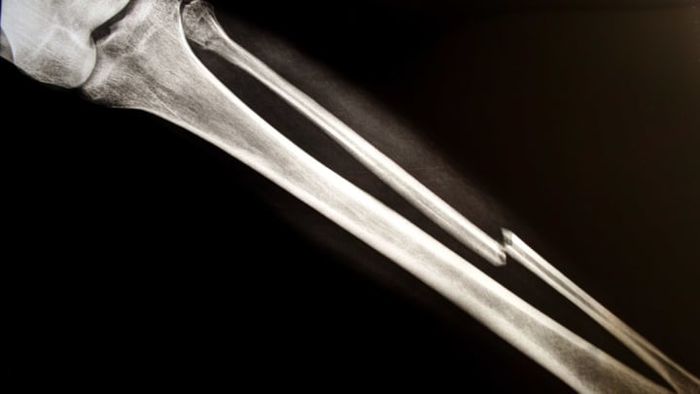

The confusion might arise because the term fracture is often used to describe certain types of breaks, such as compound fractures, oblique fractures, and comminuted fractures. However, as Henley clarifies, both break and fracture simply refer to any instance where “the normal structure of the bone has been disrupted and damaged.”

Another widespread myth surrounding broken bones is the belief that a 'clean break' is a good thing compared to other types of fractures. Dr. Henley uses the scaphoid bone in the wrist as an example, explaining that even a clean break in the 'wrong' bone can be severely problematic. In some cases, surgery may be required.